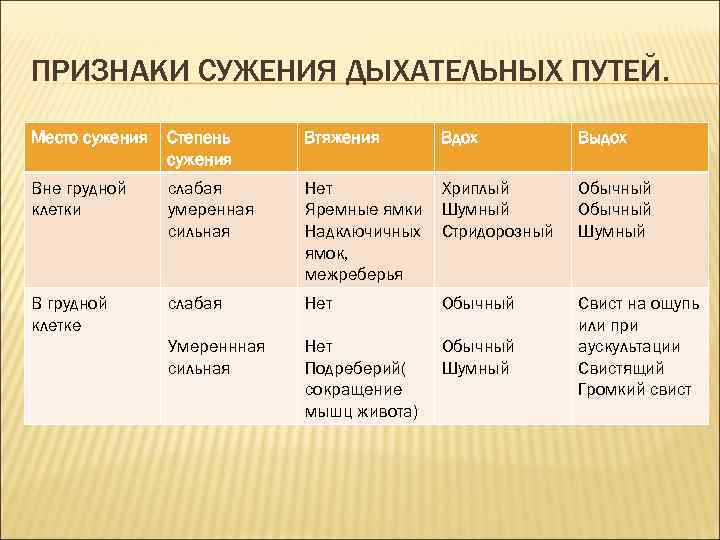

ПРИЗНАКИ СУЖЕНИЯ ДЫХАТЕЛЬНЫХ ПУТЕЙ. Место сужения Степень сужения Втяжения Вдох Выдох Вне грудной клетки слабая умеренная сильная Нет Яремные ямки Надключичных ямок, межреберья Хриплый Шумный Стридорозный Обычный Шумный В грудной клетке слабая Нет Обычный Умереннная сильная Нет Подреберий( сокращение мышц живота) Обычный Шумный Свист на ощупь или при аускультации Свистящий Громкий свист